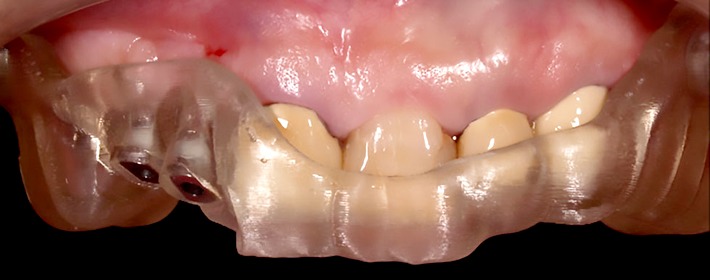

ガイデッドサージェリー